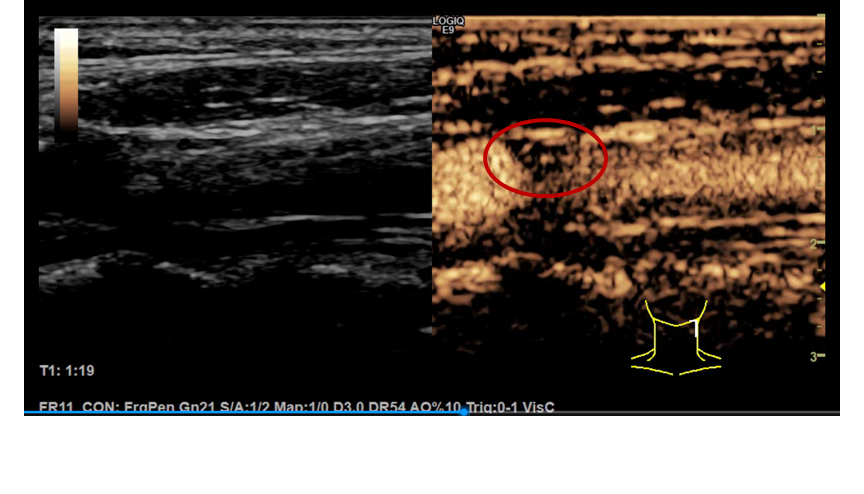

超声smi技术检测颈动脉粥样硬化斑块新生血管的应用价值

图片尺寸500x1295

a 图为颈总动脉粥样硬化的纵切图像,大箭头指向动脉壁的三层